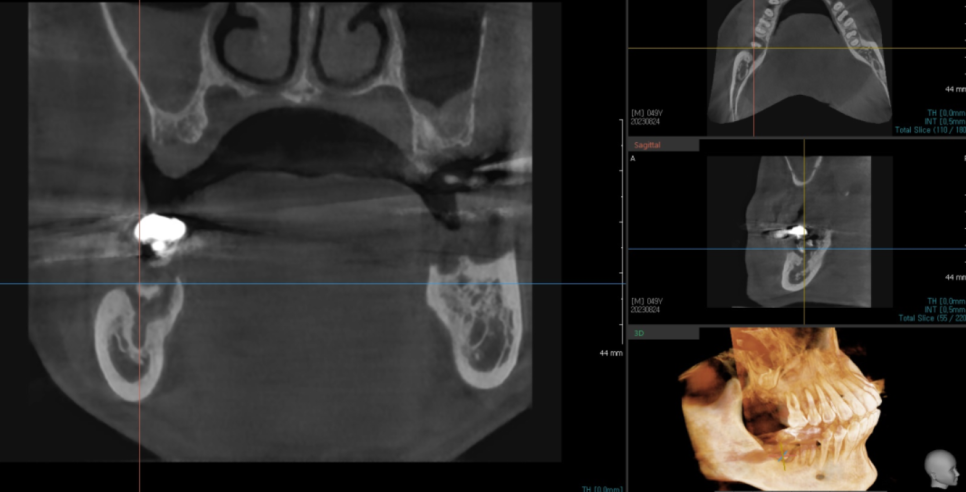

x-ray 상에서도 잇몸뼈가 많이 녹아

정밀 진단을 위해 ct 촬영을 추가로 했습니다.

진단 결과 잇몸 뼈가 거의 없었습니다.

치아를 뽑기 전 ct 사진입니다.

치아 주변으로 검정색 웅덩이를 보실 수 있죠?

이게 다 뼈가 녹은 부분입니다.